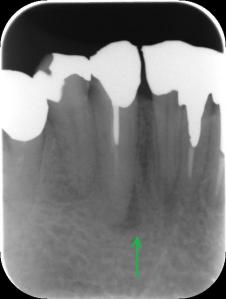

クラウンが壊れてしまっていたのか、しばらくそこに歯が入っていなかったという患者さんです。新しいクラウンが久々に入って喜んでおられますが、「ちょっと高い」とも感じておられます。

また、いまはまだ調整が完全には終わっていない段階のため、新しいクラウンは「仮止め用のセメントで付けてある」そうです。軽い違和感と、すぐにガッチリ留めてもらえなかったことが気になるのでしょうか。「先生がクラウンの製作を失敗したのではないか」と心配しておられます。

問題はむしろ、まだ慣れていない時期に、患者さんの一時的な違和感をもとに性急にクラウンを削ってガッチリ留めてしまうことです。歯科医はプロとして噛み合わせがきちっとできているかどうかを検査し、患者さん自身の使用感も大切にしながら総合的に判断していかねばなりません。本来なら削る必要のなかったクラウンを、削って止めてしまっては、最終的に噛み合わせが低くなり、せっかくのよい治療が台無しになってしまいます。

「患者さんのお口が新しいクラウンに慣れる様子を確認するまでは仮留めにしておき、次の調整で慣れの様子を見ながら最終調整して本格的に留めましょう」というやり方は、信頼のおける診療方針だと思います。